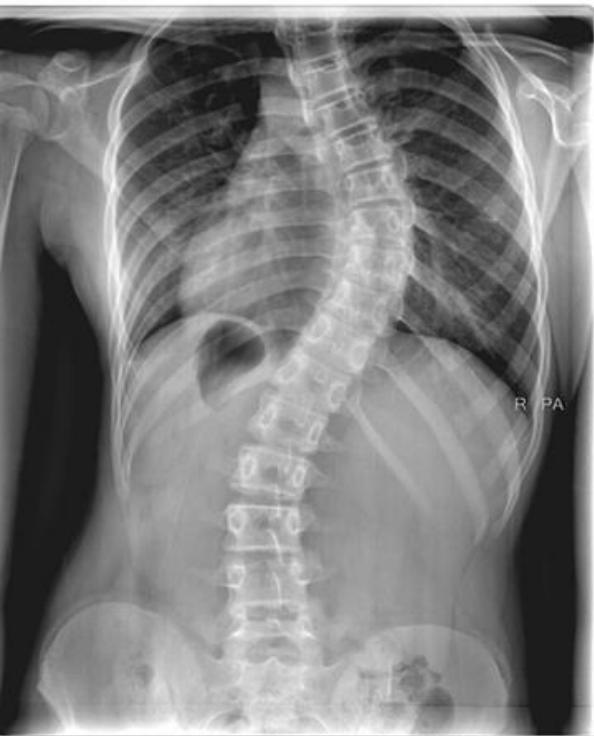

Scoliosis

Scoliosis Classification

- Adolescent Idiopathic Scoliosis

Adolescent Idiopathic Scoliosis

- Definition: Coronal plane spinal deformity most commonly presenting in adolescent girls from ages 10 to 18

Imaging:

Severity Grades:

- Mild: 10-25°

- Moderate: 25-45°

- Severe: >45°

Treatment Based on Severity:

- Observation: Mild curves, depending on age and skeletal maturity

- Bracing: Moderate curves (25-45°) in growing patients

- Surgery: Severe curves (>45°) or progressive curves